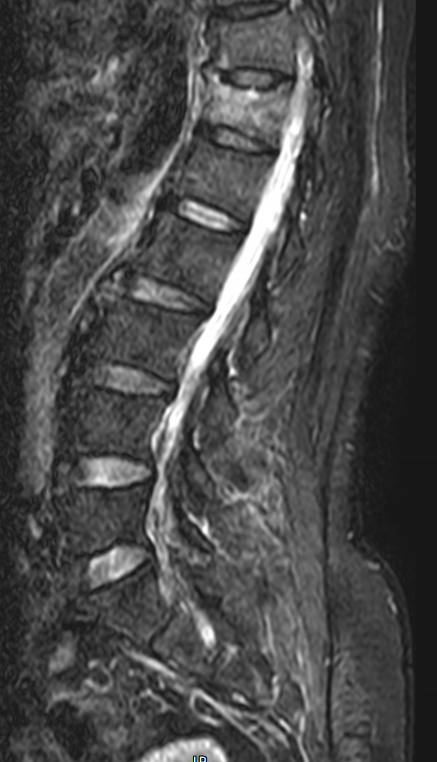

隨著老齡化社會的來臨,高齡和超高齡患者越來越多,骨質(zhì)疏松以及由此引起的骨質(zhì)疏松性脊柱壓縮骨折呈爆發(fā)式增長。脊柱是人體的主要支撐載體,相當(dāng)于房子的承重墻。一旦脊柱發(fā)生骨折,相當(dāng)于承重墻坍塌,人體的重量缺乏支撐,就會出現(xiàn)腰背部無力,疼痛,行走困難,甚至起床翻身這些動作都無法完成,只能長期臥床。PVP手術(shù)即大家熟知的骨水泥填充微創(chuàng)手術(shù),已經(jīng)有40余年的歷史,手術(shù)技術(shù)已經(jīng)十分成熟。PVP手術(shù)是一種局麻手術(shù),患者俯臥在手術(shù)臺,在骨折部位皮膚取一個(gè)3mm的小切口,用直徑2mm的專用細(xì)穿刺針從穿刺點(diǎn)進(jìn)入骨折椎體建立工作通道注射骨水泥。目前最新的手術(shù)方法是,先通過通道在骨折處置入一個(gè)金屬支架把破碎壓縮的椎體支撐起來,這樣就在骨頭內(nèi)形成了一個(gè)低壓空腔,之后再填充骨水泥,骨水泥就會在低壓區(qū)積聚不易滲漏,骨水泥和金屬支架混合,只需要5分鐘即可凝固硬化,永久維持、支撐骨頭的形態(tài),骨折復(fù)位更好、固定更牢靠,就相當(dāng)于用“鋼筋混凝土”把人體的“承重墻”徹底牢固的修復(fù)好了,“承重墻”修復(fù)好后,患者馬上就感覺腰部有力、疼痛緩解、起床翻身就會輕松很多,術(shù)后2小時(shí)就可以下地行走了。—“鋼筋混凝土”強(qiáng)化治療脊柱骨折